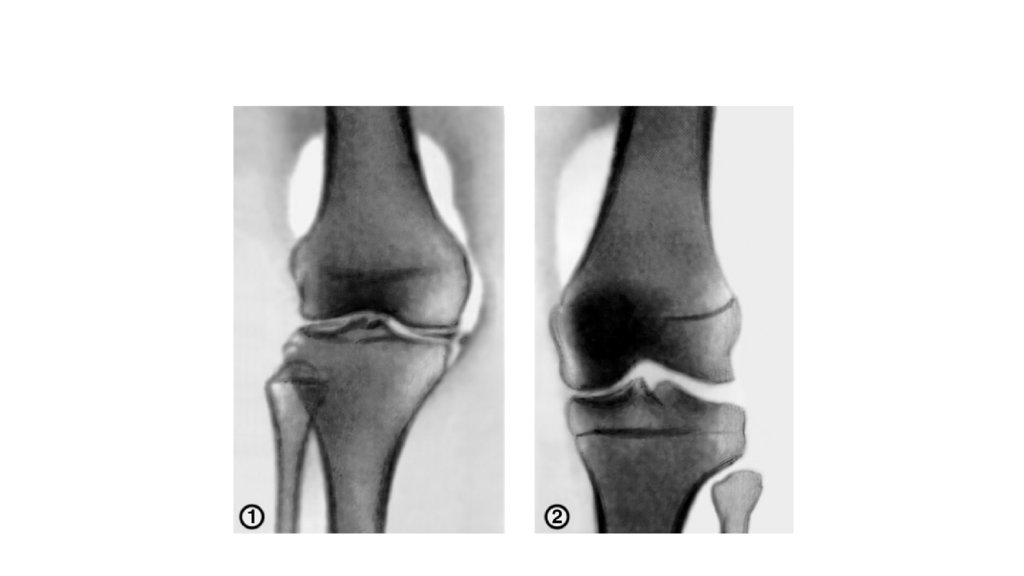

Какие процедуры/методы осмотра(обследования) изображены на фото?